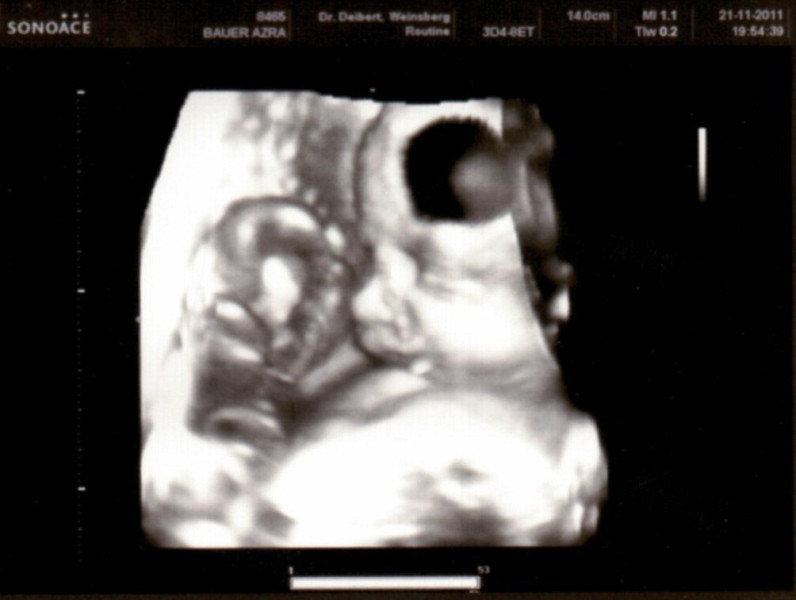

Sono-Pics vom Junior

Auch wenn er sich nicht gerne fotografieren läßt (ganz die Mama) haben wir doch ein paar Schnappschüsse von ihm.